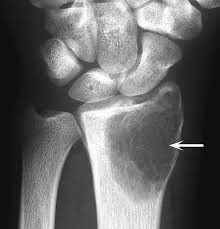

Giant cell tumors of bone commonly occur in the metaphysis and vertebral bodies of long bones, such as the lower end of the femur and the upper end of the tibia. Patients may have no obvious symptoms in the early stages of the disease, but as the disease progresses, symptoms such as pain, swelling, and limited joint movement will gradually appear. These symptoms are closely related to the growth rate and invasion range of the tumor.

The diagnosis of giant cell tumor of bone mainly relies on imaging examinations (such as X lines, CT, MRI, etc.) and pathological examinations. Imaging examination can show the size, location and extent of invasion of the tumor, while pathological examination can determine the nature and grade of the tumor.